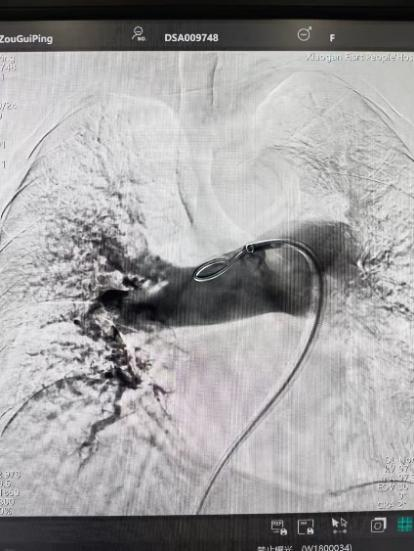

面對(duì)危急的病情,介入血管科團(tuán)隊(duì)在黃遷祥的帶領(lǐng)下,對(duì)患者病情進(jìn)行充分評(píng)估和綜合研判后,最終制定了 “肺動(dòng)脈抽栓 + 局部溶栓藥物灌注 + 下腔靜脈濾器置入術(shù)” 的微創(chuàng)介入治療方案。

術(shù)前

術(shù)后

手術(shù)在局部麻醉下進(jìn)行,團(tuán)隊(duì)通過(guò)股靜脈穿刺,將專(zhuān)用抽栓導(dǎo)管精準(zhǔn)送達(dá)肺動(dòng)脈栓塞部位,利用負(fù)壓抽吸技術(shù)成功清除大量血栓;隨后,在血栓局部精準(zhǔn)灌注溶栓藥物,進(jìn)一步溶解殘余血栓,恢復(fù)肺部血流灌注;同時(shí),為防止下肢深靜脈血栓再次脫落引發(fā)肺栓塞,團(tuán)隊(duì)為患者置入下腔靜脈濾器,整個(gè)手術(shù)歷時(shí)約1小時(shí)。術(shù)后,鄒婆婆呼吸困難癥狀即刻得到緩解,血氧飽和度顯著提升,右心負(fù)荷明顯減輕,目前身體狀況正在逐步恢復(fù)中。